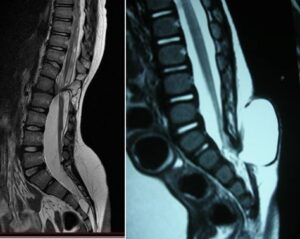

This generally occurs due to the spinal cord becoming tethered to surrounding structures at the level of the malformation, which, as the patient grows, leads to progressive stretching of the cord itself.

The orthopedic surgeon’s task is to suspect that these deformities are secondary to spinal dysraphism and initiate investigations (electrophysiological tests, MRI, etc.) for these pathologies.